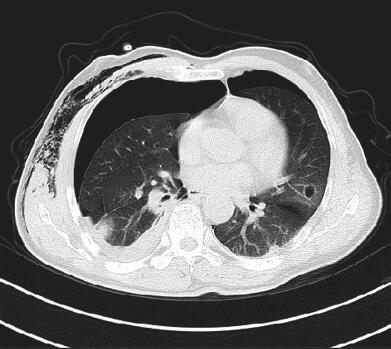

图3 2014年12月21日胸部CT

左舌段空腔病灶较前增大,左下叶基底段出现疑似空洞病灶,病灶周边可见斑片影,双侧气胸,以右侧为主